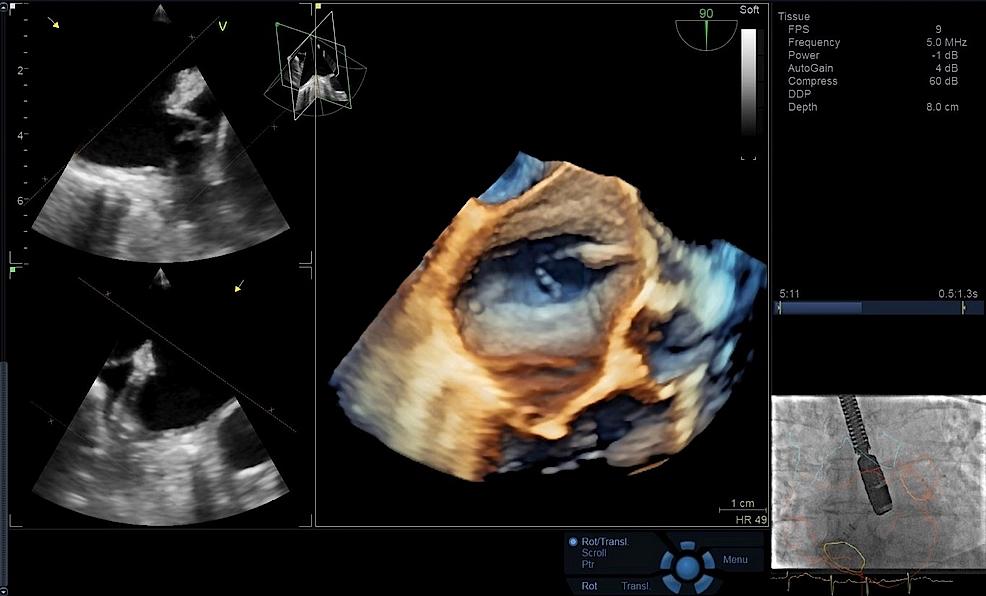

FlexiLight

Rendering techniques for photo-realistic

light-source based illumination of heart

structures, providing comprehensive

visualization of cardiac structures.

FlexiLight may allow a comprehensive

visualization of leaflets and regurgitant

orifices while ensuring the proper

alignment of the clip towards the mitral

valve annulus.